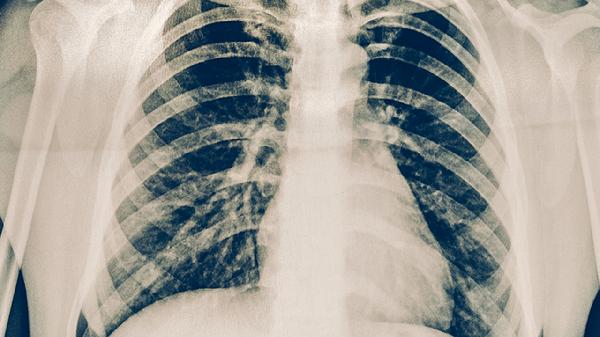

在极少数情况下,鼻病毒感染也可能导致病毒性肺炎,这种情况多发生在免疫系统严重受损的人身上。患者可能会出现持续高烧、呼吸急促以及血氧水平下降等症状,需要通过胸部CT和病原体检测来明确诊断。早产儿、未接种疫苗的儿童、长期服用免疫抑制药物的人,都属于高风险群体,应特别注意防护。